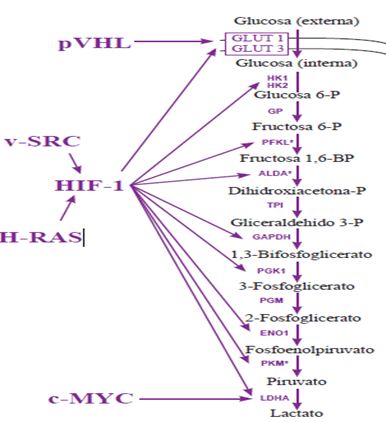

El factor HIF-1 se une a unas determinadas secuencias de más de 70 genes de manera directa y más de 200 genes de manera indirecta, con tal de estimular la producción de proteínas codificadas por esta (Werger, 2006). Estas proteínas están involucrados en diferentes procesos importantes como podrían ser: angiogénesis (generación de nuevos vasos capilares), eritropoyesis, trasporte de glucosa, transporte de hierro, activación de la glucólisis, proliferación y viabilidad celular, remodelación vascular, respuestas vasomotoras… entre otras (Werger, 2006). Con estos no nos extrañamos de sus importancia en ciertos estados fisiológicos como fisiopatológicos.

Figura 1. Implicación de factor HIF-1 en las rutas metabólicas glucolíticas (González, 2007).